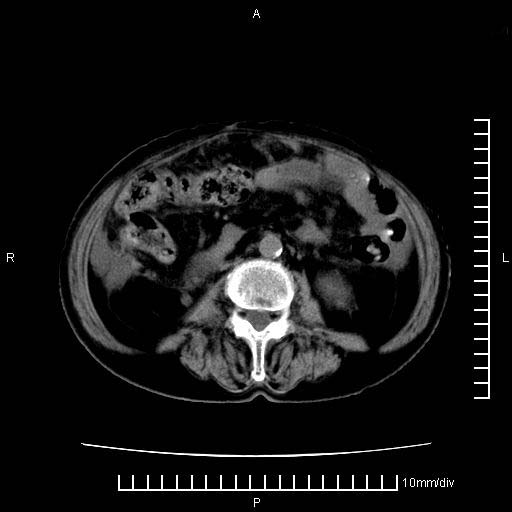

标题: CT28280:腹部增强:女性,80岁

上腹疼痛月余,外院核磁诊断胰腺癌。现临床示右下腹可明显触及包块,可片子上怎么没有看到?

1.胰腺颈体部癌。

2。腹腔积液。

3。右胸腔积液,伴右肺下叶部分萎陷。

4。右肾盂囊肿。

胰腺体部癌累及周围器官,腹膜、粘连

1。胰腺ca伴腹膜腔转移

2。肝左叶低密度灶,考虑转移可能

胰腺体部癌累及周围器官,腹膜、粘连,临床摸到的可能是粘的组织

胰腺结构模糊,胰尾部见囊性包块,周围脂肪密度增高,左肾前筋膜增厚,胸水、腹水。不符合胰腺ca伴腹膜腔转移。考虑胰腺炎伴假性囊肿形成、胸腹腔积液。

右肾盂囊肿。

1)考虑胰腺癌并胰腺假性囊肿形成。2)肝内低密度灶,不排除转移。3)右肾盂积水。4)腹水。5)右侧胸腔积液并右肺下叶部分膨胀不全。